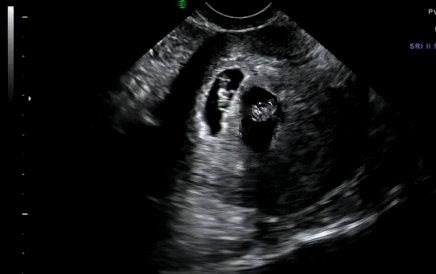

AGnesssssss ale się cieszę!!!!!!!!!!!!!!!!!!!!!!!czekamy na fotke :-)Witam wszystkie własnie wracam z USG no i musze sie pochwalić, za chwile wrzuce fotke:-):-) az mi sie rece trzęsą jeszcze do mnie nie dociera

, ale jedna czy dwie fasolki są ????????

agnesssss śliczna, ale jedna czy dwie fasolki są ????????